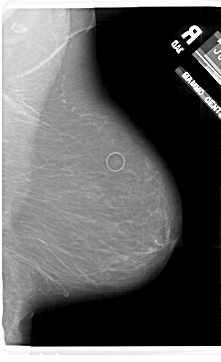

A_1802_1.LEFT_MLO

LEFT_MLO LINES 6871 PIXELS_PER_LINE 4216 BITS_PER_PIXEL 12 RESOLUTION 43.5 OVERLAY

FILE: A_1802_1.LEFT_MLO.OVERLAY

TOTAL_ABNORMALITIES 1

ABNORMALITY 1

LESION_TYPE MASS SHAPE ASYMMETRIC_BREAST_TISSUE MARGINS ILL_DEFINED

ASSESSMENT 4

SUBTLETY 5

PATHOLOGY BENIGN

TOTAL_OUTLINES 1

BOUNDARY